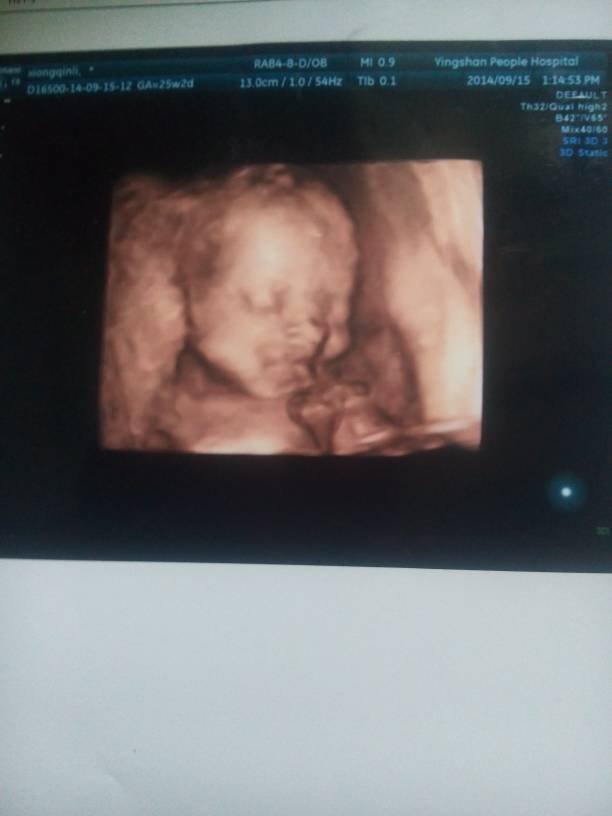

四维顺利归来,宝妈们,帮我看看男女 四维顺利归来,宝妈们,帮我看看男女 点击展开 双鱼座女孩! 2014-09-15 17:24 为您推荐: 其他回答 看不出来的 我爱我的一家 2014-09-15 17:28 没有看见生殖器,孕期国家法律规定禁止非医学需要的胎儿性别鉴定,一般是不知道的。 jy3130376 2014-09-15 17:26 相关问题 四维彩超归来,有那个宝妈会看男女 帮忙看一下 请问有宝妈会不会看孕囊看出男女的吗?帮我看看、谢谢了 今天四维检查顺利通过,可是医生说宝宝比实际孕周小两周,有宝妈也这种情况的吗?